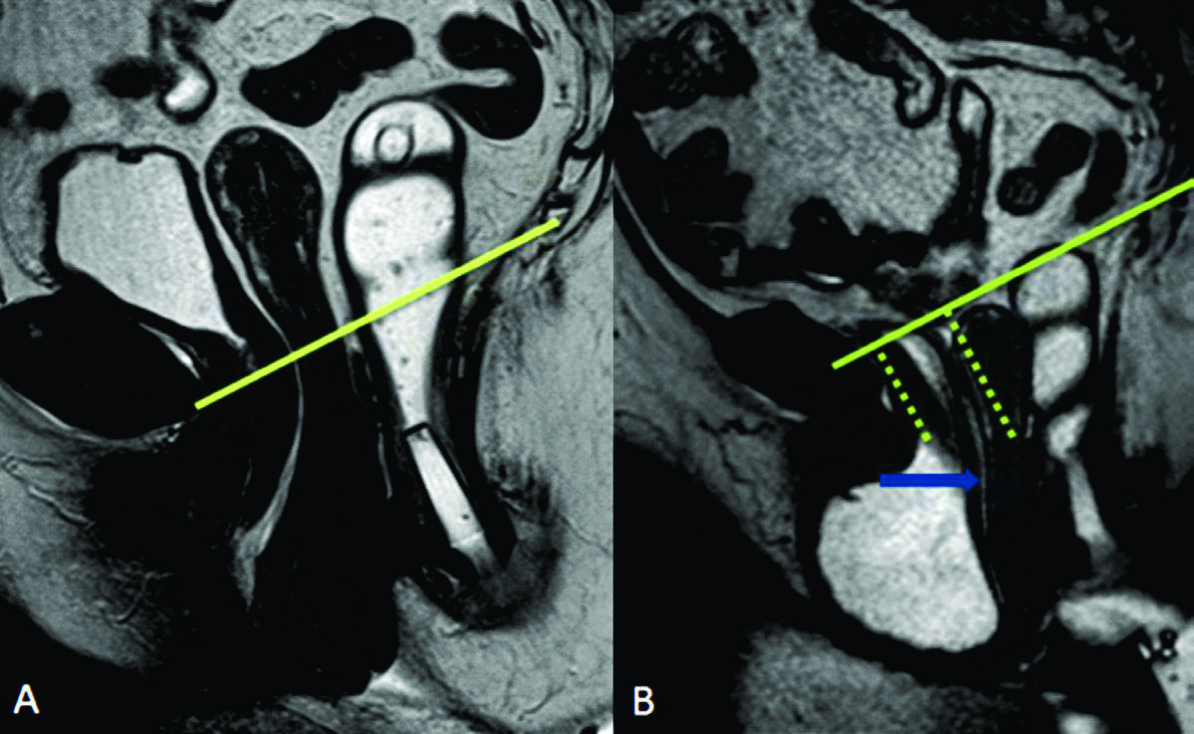

Figura 6

Cistocele,

pequeño rectocele anterior y prolapso de la cúpula vaginal. Imágenes TRUE FISP de alta resolución en el plano sagital a nivel de la línea media de una mujer durante A) el reposo y durante B) la defecación. Prolapso de la cúpula vaginal (triangulo en b) y rectocele anterior (estrella en B). Las líneas punteadas en verde miden la severidad de los prolapsos.